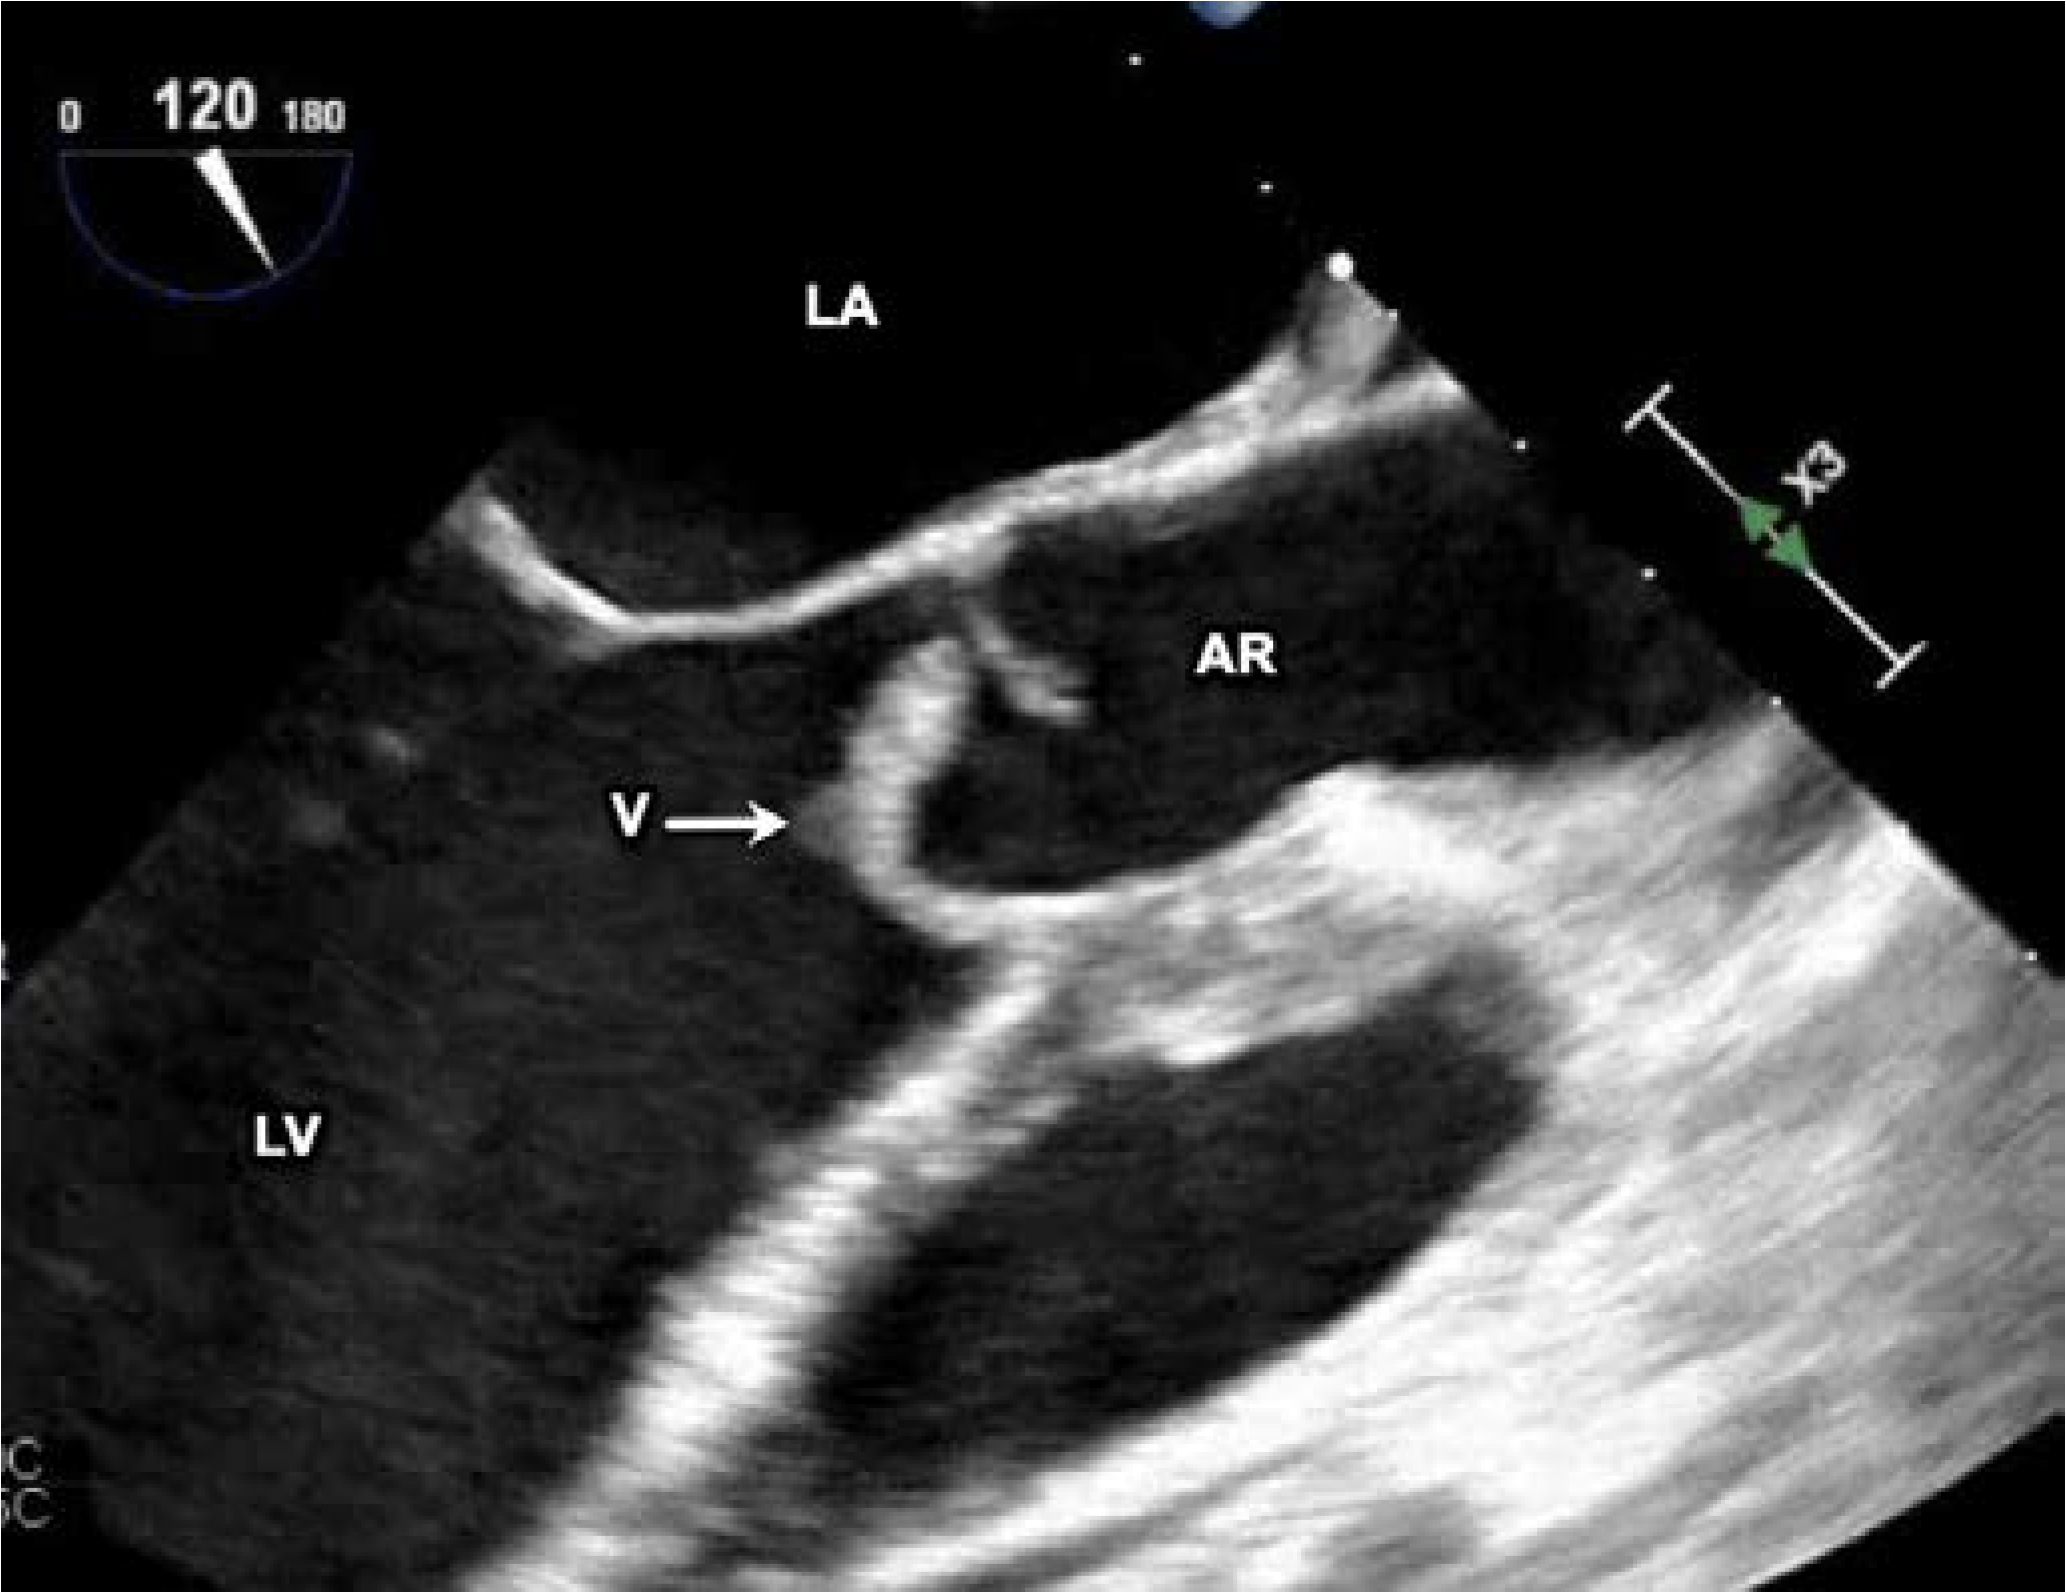

Initial surface echocardiography showed a bicuspid aortic valve with thickening of the right cusp and a small nodule suspicious for a vegetation, with mild eccentric aortic regurgitation. Transesophageal echocardiography (Figure 1) redemonstrated the bicuspid aortic valve, but with a large mobile echogenic mass measuring 1.6 cm on the right coronary cusp, with severe aortic regurgitation, an aortic root abscess (Figure 2), and evidence of right coronary leaflet prolapse into the left ventricle with associated perforation.

Figure 1. Transesophageal echocardiogram, showing the vegetation on the aortic valve. AR—aortic root; LV—left ventricle; LA—left atrium; V—vegetation.

In our case, the patient presented with acute endocarditis with a large mobile mass, associating with severe aortic regurgitation, an aortic root abscess and an associated perforation.